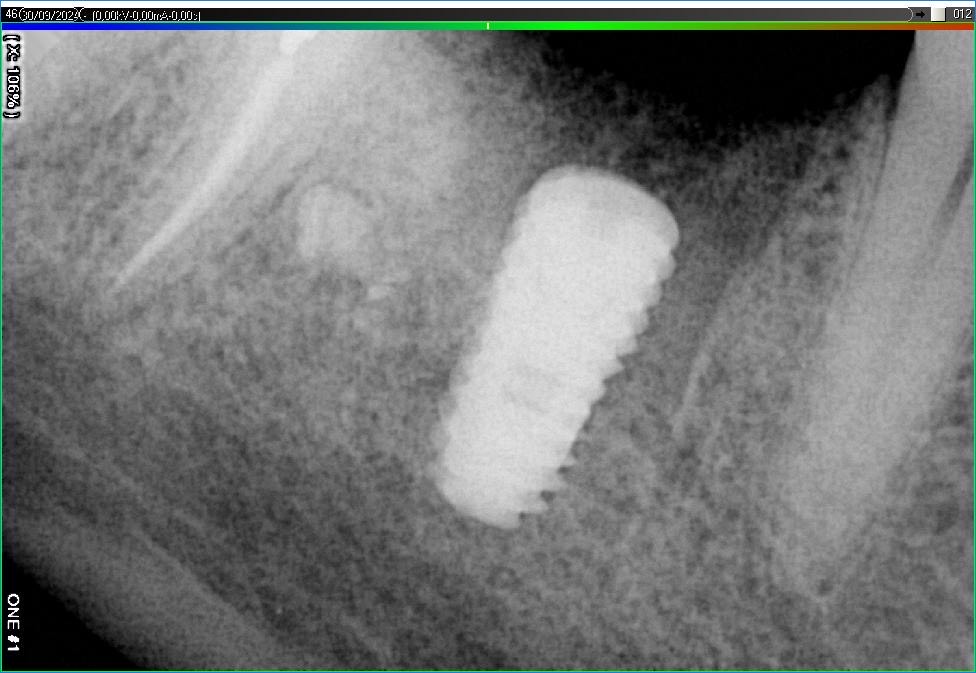

Імплантація